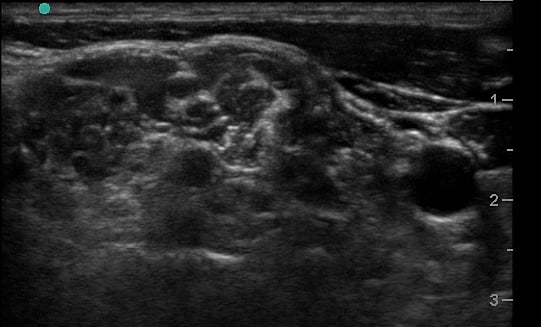

- Visualize the brachial plexus here as a stack of circles with hypoechoic centers

- The plexus will look more echogenic, bundled and honeycombed in the caudal interscalene space

- The brachial plexus is seen immediately adjacent to the superior-posterior border of the subclavian artery as a grouping of small hyperechoic circles with hypoechoic centers, similar to a cluster of grapes.

- Backtrack from this site to the interscalene space by sliding the probe cephalad while keeping the plexus in the center of the image.

- The plexus will change conformation and become more hypoechoic as you slide superiorly.